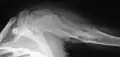

| X-ray image showing enchondromas localized in the lower part of the radius of a 7-year-old girl with Ollier disease. | |

Abnormal bone growth such as shortening or thickening and deformity may be observed in patients of Ollier disease. These bone lesions are visible at birth using radiography but are usually not screened or examined for until clinical manifestations present during early childhood. However, some patients may exhibit no signs of any symptoms.[1] One study found thirteen to be the mean age of diagnosis in patients with Ollier disease. In an X-ray, there would normally be the presence of several homogeneous lesions of an oval or elongated shape with bone edges that are slightly thickened.[3] With age, these lesions may calcify and appear as diffusely minute spots or stippled. Fan-like septations or streaks would be indicative of the presence of several enchondromas. Early detection and consistent and repeated monitoring is important in order to prevent and treat any potential bone neoplasms.